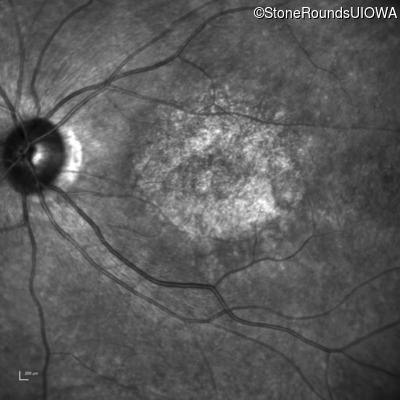

AR Stargardt Disease (IIA)

AR Stargardt Disease (IIA)

| Age at visit: 12 years |

| Age at visit: 13 years |

| Age at visit: 15 years |